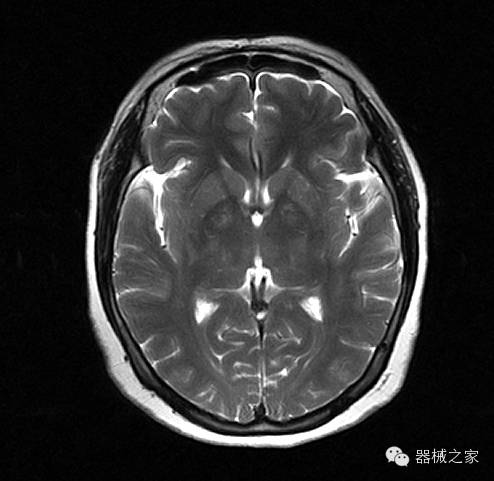

临床图片赏析

头部SWI

头部SWIM(定量分析)

腹部组图 T1WI(Out Phased)、T2WI(FS)、THRIVE、DWI